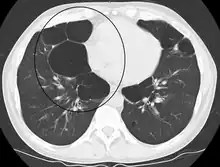

Section of a lung showing centrilobular emphysema, with enlarged airspaces in the centre of a lobule usually caused by smoking and a major feature of COPD